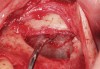

The technique described below is based on a deep buccal full-thickness flap with vertical release in the canine area, followed by creation of a “window” at the lateral wall of the sinus (Figure 2). The bony window is either removed or rotated medially with the sinus membrane and pushed inward. The Schneiderian membrane is then separated from the bone anteriorly, posteriorly, and medially until clinically sufficient space is established (Figure 3). The created space, which occupies the lower third of the sinus, is filled with a bone graft (Figure 4), and the lateral access window is covered with a collagen membrane (Figure 5).

Fig 2. Lateral approach to sinus floor augmentation steps. Full-thickness flap elevated and the outline of the lateral window is marked.

Figure 2

Fig 3. Schneiderian membrane from the sinus walls is elevated.

Figure 3